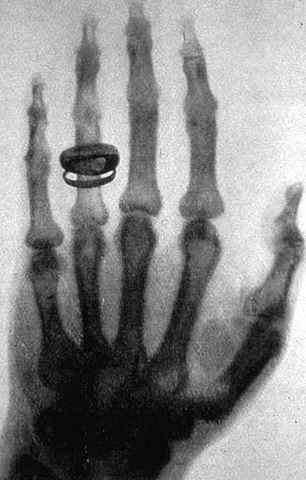

• La primera aplicacion medica de los rayos X

La primera aplicacion medica de los rayos X

W. Conrad se decide a realizar su primera prueba en humanos, para lo que pide la colaboración de su esposa Berta, a quien le indicó que mantuviera la mano en la placa durante 15 minutos.